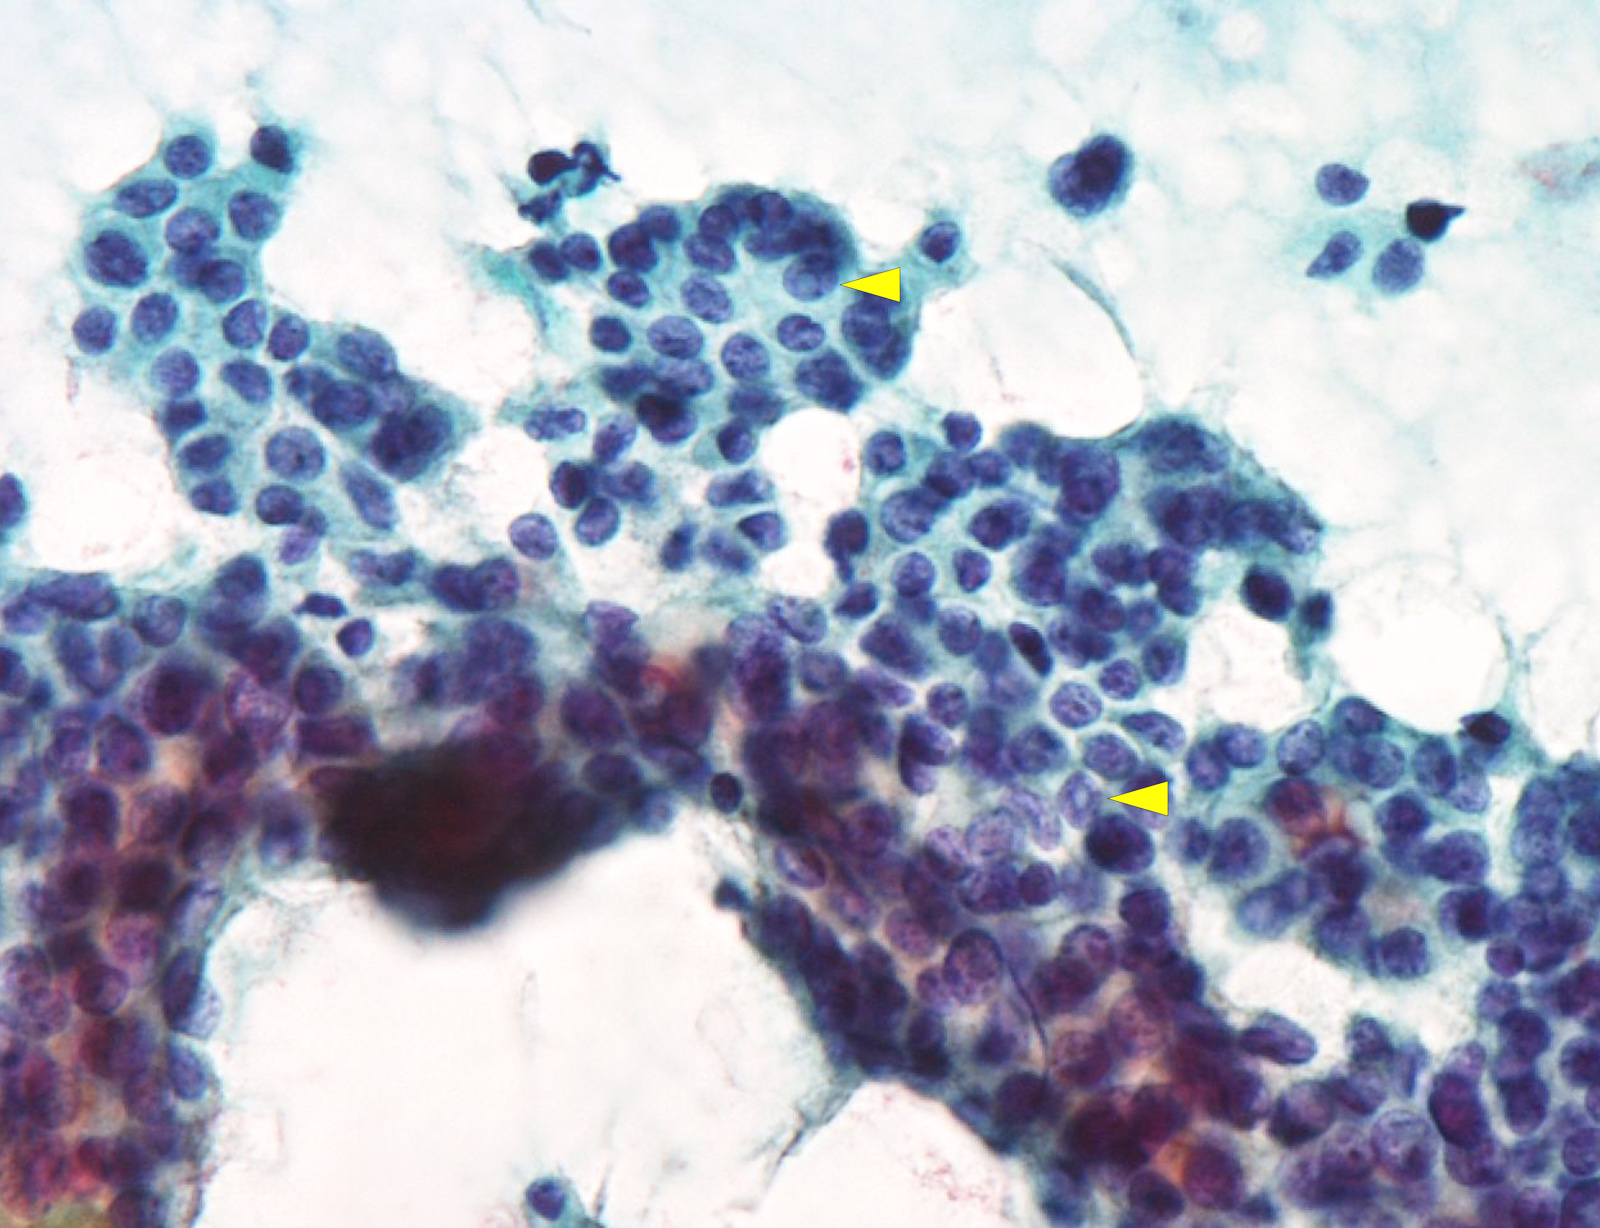

Cytology description

- Hypercellularity

- Small, round and dense colloid (hyaline colloid) may be present, sometimes within follicles

- Cells arranged in microfollicles or trabecular pattern

- Nuclear enlargement but may lack prominent nuclear features of papillary carcinoma (Am J Clin Pathol 1999;111:216)

- Highly suggestive of syncytial clusters, microfollicular architecture, chromatin clearing and nuclear grooves (Acta Cytol 2006;50:663)

- Classified by Bethesda system as categories III to VI

- Cytologically unable to distinguish between noninvasive and invasive

Cytology images

Contributed by Ayana Suzuki, C. T.